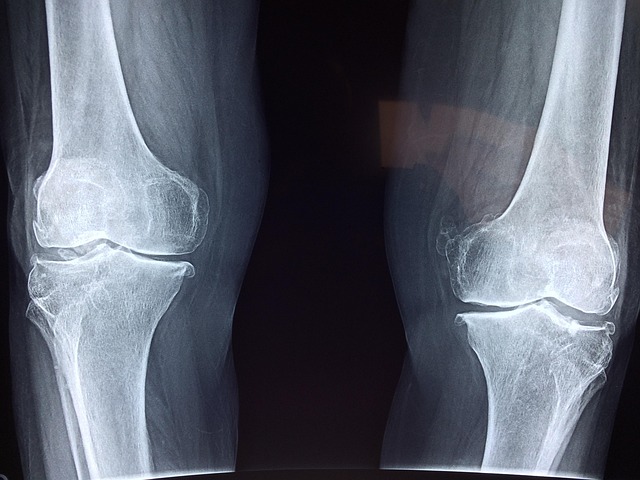

골다공증은 남녀 모두에게 발생할 수 있는 질환이지만, 특히 여성, 그중에서도 폐경기에 접어든 중년 여성에게서 높은 유병률을 보이는 특징이 있습니다. 그 이유는 바로 여성 호르몬, 특히 에스트로겐의 급감이 골밀도 손실에 직결되기 때문입니다. 여성은 폐경 이후 5~10년 동안 급격한 골 소실이 진행되며 이는 남성보다 2배 이상의 속도로 진행될 수 있습니다. 이 시기의 뼈는 작고 가벼운 외부 충격에도 쉽게 골절되며 특히 척추, 고관절, 손목 등에서 흔히 골절이 발생합니다. 골다공증은 조용한 도둑이라고 불릴 만큼 증상이 나타나지 않다가 어느 날 갑작스러운 골절로 확인되는 경우가 많아 조기 진단과 예방이 필수적입니다. 특히 중년 여성은 생리적 특성 외에도 칼슘 섭취 부족, 활동량 감소, 흡연, 음주, 낮은 체중 등의 위험 요인을 동반하는 경우가 많아 예방이 더욱 중요합니다. 40대 후반부터는 골밀도 검사(BMD)를 정기적으로 시행하며 자신의 골 건강 상태를 파악하고 관리 방안을 세워야 합니다. 더불어 골다공증은 단순한 뼈의 문제를 넘어 삶의 질을 위협하는 심각한 문제로 이어질 수 있습니다. 척추 압박 골절은 키 감소나 만성 요통으로 이어질 수 있고 고관절 골절은 장기 입원과 후유증, 심하면 사망률 증가로도 이어질 수 있기 때문에 단순히 나이 들면 생기는 것으로 치부할 수 없는 질환입니다. 지금 이 시점에서 중년 여성의 골다공증을 예방하기 위한 근거 기반의 접근이 반드시 필요합니다.

골다공증 예방의 첫걸음은 균형 잡힌 식단 관리입니다. 무엇보다 칼슘과 비타민 D 섭취가 매우 중요합니다. 칼슘은 뼈를 구성하는 주요 무기질로, 하루 1,000~1,200mg의 섭취가 권장되며, 유제품 외에도 멸치, 두부, 브로콜리, 참깨 등을 통해 보충할 수 있습니다. 비타민 D는 칼슘의 흡수를 돕는 필수 영양소로 일조량이 적은 계절에는 식이로 충분히 보충하기 어렵기 때문에 보충제를 병행하거나 하루 15~30분 정도 햇빛을 쬐는 것이 효과적입니다. 둘째는 운동 습관의 형성입니다. 뼈는 자극이 있어야 강해지는 조직으로 적절한 체중 부하 운동과 근력 운동이 매우 중요합니다. 특히 빠르게 걷기, 계단 오르기, 가벼운 조깅, 요가, 필라테스 등은 뼈에 긍정적인 자극을 주며 주 3~5회 이상 꾸준히 실천하는 것이 이상적입니다. 또한 근력 운동은 뼈와 근육을 동시에 강화해 낙상과 골절의 위험을 낮추는 데 효과적입니다. 운동 전에는 반드시 스트레칭을 통해 부상을 예방하고 운동 후에는 충분한 휴식과 영양 공급이 병행되어야 합니다. 셋째는 생활습관의 점검입니다. 흡연은 골밀도를 감소시키는 주요 요인 중 하나이며 지나친 음주 역시 칼슘 대사를 방해하고 뼈의 회복력을 저하시킵니다. 카페인 섭취가 과도한 경우에도 칼슘 배출이 증가하기 때문에 하루 2잔 이내로 제한하는 것이 바람직합니다. 체중이 너무 낮거나 극단적인 다이어트를 반복하는 경우 골밀도가 급감할 수 있기 때문에 적정 체중 유지를 위한 건강한 식습관이 중요합니다. 더불어 정기적인 골밀도 검사는 자신의 골 건강 상태를 정확히 파악하고 적절한 시기에 치료나 보충을 시작할 수 있는 중요한 지표가 됩니다. 특히 가족력이나 과거 골절 병력이 있는 여성과 폐경 후 5년이 지난 여성은 연 1회의 골밀도 검사를 권장합니다. 조기 발견은 곧 조기 관리로 이어질 수 있는 지름길입니다.